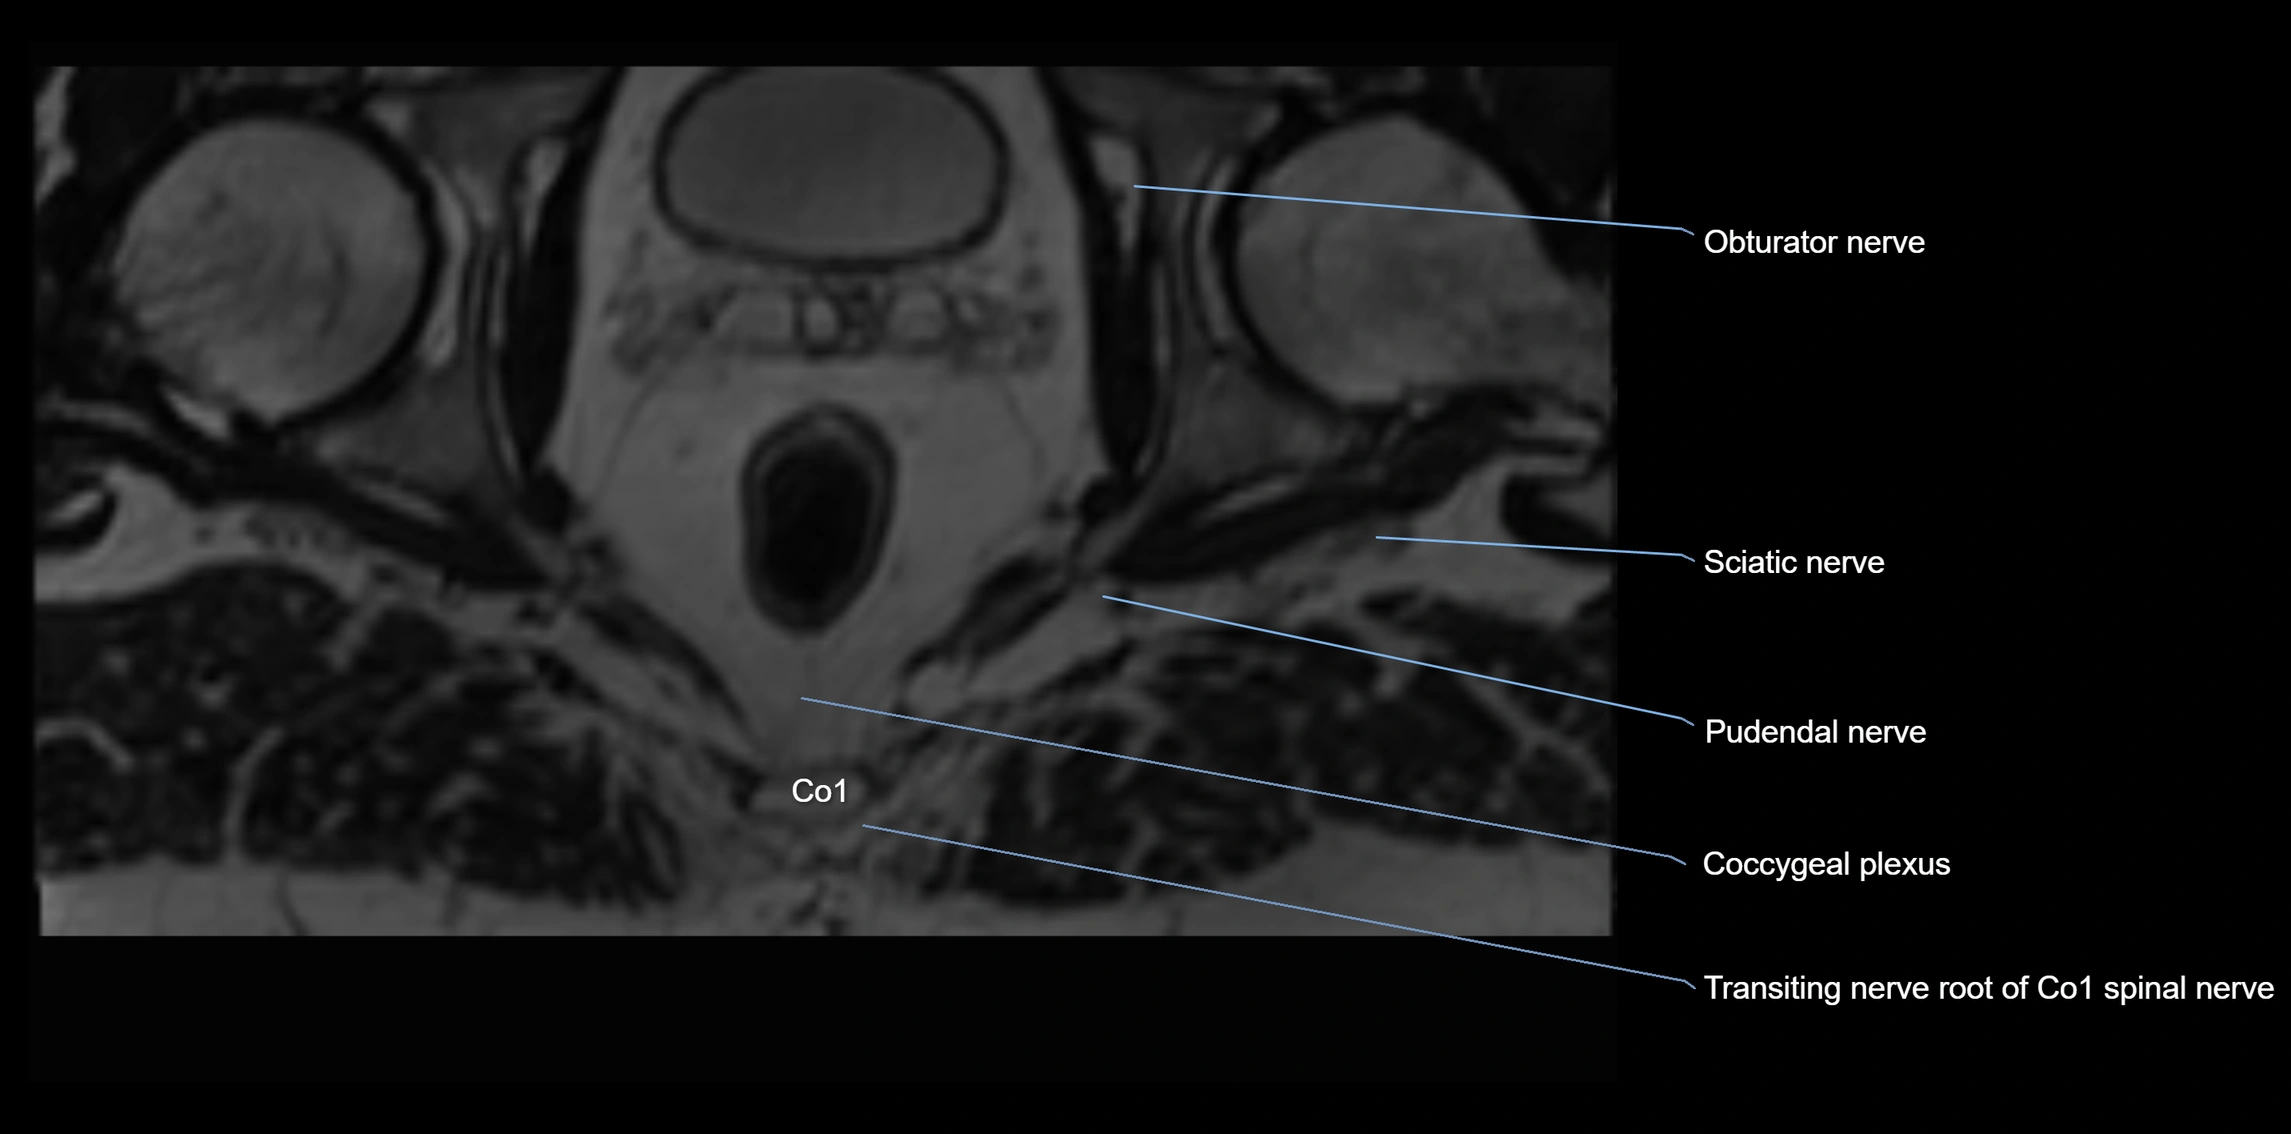

Anococcygeal nerve

The anococcygeal nerve is a small sensory nerve derived from the coccygeal plexus, which itself is formed by the ventral rami of S4, S5, and the coccygeal nerve (Co1). Although tiny, this nerve plays an important role in supplying the skin of the coccyx and the area between the anus and coccyx. It passes through the sacrotuberous ligament and runs in the midline behind the coccyx.

Despite its small size, the anococcygeal nerve is clinically important because of its involvement in coccygodynia (coccyx pain) and perineal pain syndromes.

Origin, Course, and Branches

• Origin:

• Arises from the coccygeal plexus, formed by ventral rami of S4, S5, and Co1

• Course:

• Emerges through the sacrotuberous ligament near the coccyx

• Runs in the midline posterior to the coccyx

• Passes forward into the small space between anus and coccyx

• Branches:

• Small cutaneous branches that supply the skin between the coccyx and anus

Relations

• Anteriorly: Coccyx and sacrococcygeal joint

• Posteriorly: Skin of sacrococcygeal region

• Laterally: Sacrotuberous ligaments

• Inferiorly: Perianal skin and pelvic floor muscles

MRI Appearance

T1-weighted images:

• Nerve appears as a very thin low-to-intermediate signal intensity structure

• Surrounded by bright fat, aiding visualization

T2-weighted images:

• Nerve shows intermediate to mildly hyperintense signal compared to muscle

• Pathological involvement appears brighter

STIR (Short Tau Inversion Recovery):

• Normal nerve appears dark

• Inflamed or entrapped nerve appears bright hyperintense

T1 Fat-Sat Post-Contrast:

• Normal nerve enhances minimally

• Pathologic nerve (neuritis, entrapment, tumor infiltration) shows focal or diffuse enhancement

3D T2 SPACE / CISS:

• Nerve appears intermediate to mildly hyperintense compared to muscle

• Surrounded by bright fat or CSF, improving visualization

• Best sequence for mapping small pelvic nerves such as the anococcygeal